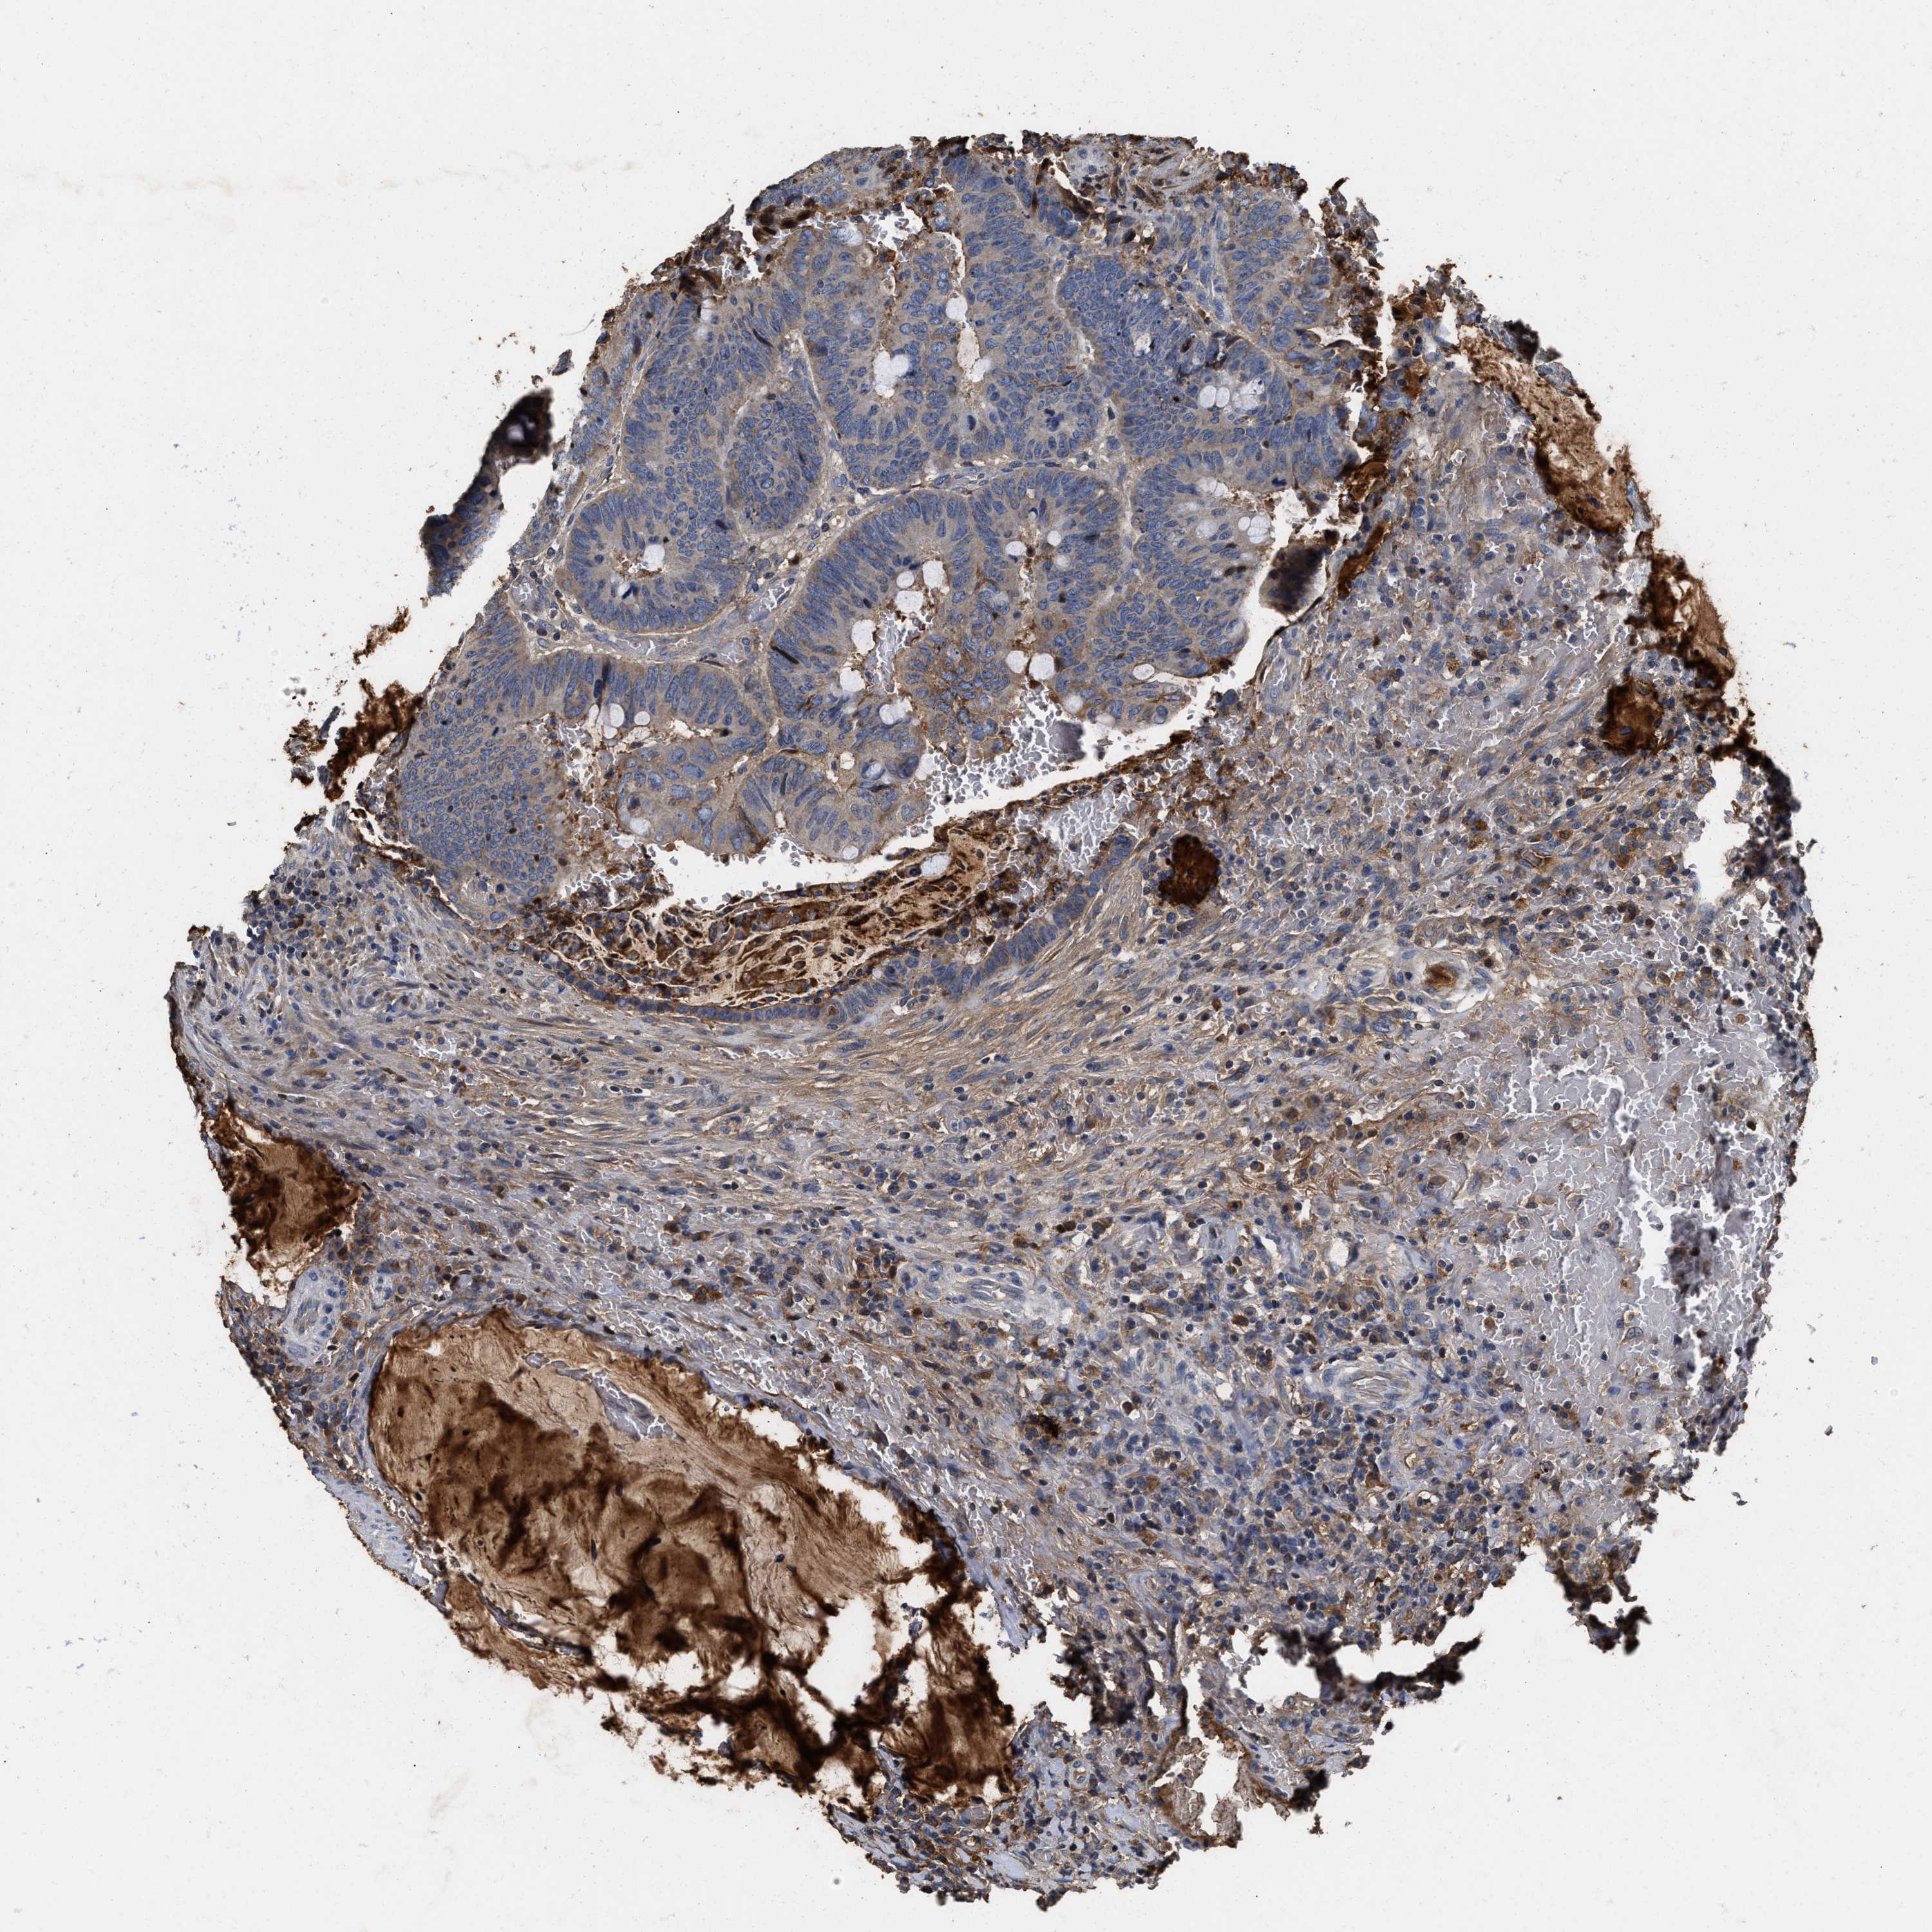

CANCER COLORECTAL CANCER Show tissue menu

Colorectal cancer

Human cancer

Colon adenocarcinoma

COAD TCGA COAD VALIDATION READ TCGA READ VALIDATION PROTEIN COAD CPTAC PROTEIN EXPRESSION